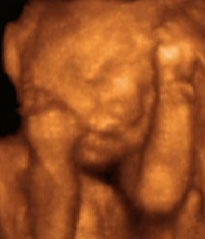

Mivel mindig kedden kapom meg az aktuális hírlevelet, így a pocakfotók után következzen Kicsi Bohne fejlődésének következő lépése:

24. hetes ultrahang képMár működnek gyermeked bőrének faggyú és izzadtságmirigyei. Most már tökéletesen láthatók az ujjkörmei, a lábkörmei, a szemöldökei és szempillái, amelyek egészen a születéséig növekedni fognak. Már tökéletesen reagál a hangokra, jól hall téged és azokat, akik körülötted élnek, dolgoznak. Bár azt hisszük, hogy az anyaméh csendes hely, igazából már eddig is rengeteg hang, zaj vette körbe magzatod. A szívverésed, emésztésed zajai, más testi funkciók hangjai, és ezek mellett a kívülről érkező hangok. Hirtelen zajokra akár meg is ugorhat gyermeked. Most már 36 centi körül mozog hosszban, súlya már majdnem egy egész kiló!

A méhedben a sötétség sem örök, némi fény átjut bőrödön és szöveteiden, de ez pont elég ahhoz, hogy gyermeked érzékelje a fény és sötét váltakozását. A baba bőre ráncos, áttetsző, és kissé vöröses is, mivel már a bőr véredényei is kifejlődtek. Vénái és ütőerei tökéletesen látszanak még a bőr alatt, bár lassacskán áttetszőből opálossá válik a bőr, ahogy a következő hónapban egyre több zsír halmozódik fel alatta. Tüdejében most fejlődnek a hörgőcskék, és elkezdődik azoknak a felületaktív anyagoknak a termelődése is, melyek születése után majd segítik a tüdők kitágulását. A létfontosságú szervek már kifejlődtek, 10 babából azonban még mindig csak négy élné túl a megszületést komoly orvosi segítséggel.

Azért még mindig maradjon a kuckójában Kicsi Bohne Baba, élvezze csak anyukája 5 csillagos szervízét. :))) Ma bejelentkeztem Sopronba is 4 dimenziós ultrahangra, majd 27-én, kedden délelőtt megyünk egyet babamozizni, remélem hogy megmutatja majd nekünk az arcocskáját, hogy utána már tudjunk találgatni, kitől örökölte az orrát, a száját, a pofikáját stb... :))) Már várom nagyon. De addig még jövő hétfőn nődoki látogatás, ott is kicsit megleshetjük, csak a dokimnak nem igazán jó minőségű az ultrahang masinája, amit az is bizonyít, hogy ő az egyedüli, ahol nem láttunk eddig még kukacot, viszont mindenhol máshol elég egyértelmű bizonyítékot kaptunk arról, hogy Kicsi Bohne ÚRFI érkezik hozzánk. :))